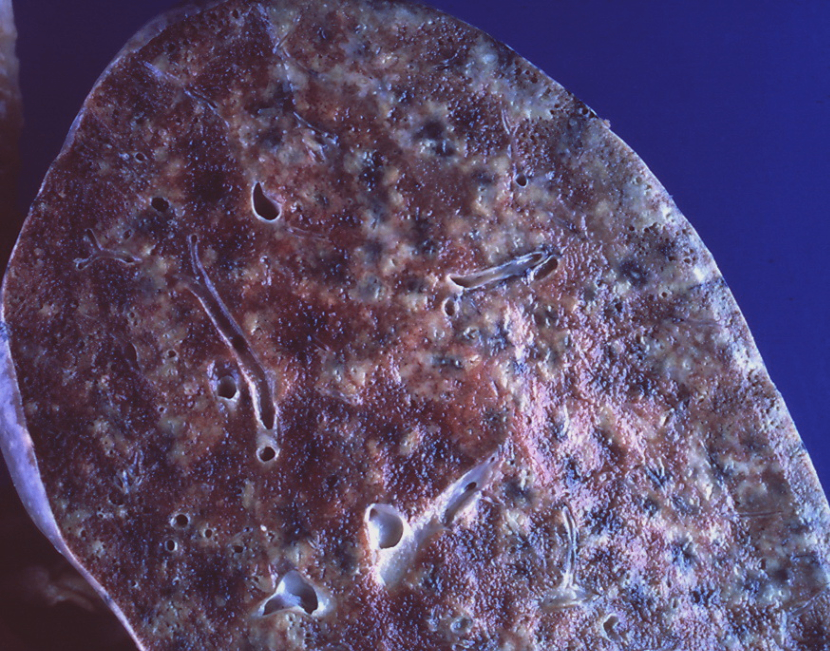

④ 속립결핵 (military tuberculosis)

결핵균이 혈생성 전파를 통해 전신으로 퍼짐

2 mm 크기의 속립 모양의 황색 병소들이 간, 비장, 골수, 폐, 부신, 고환 등에서 광범위하게 발견됨

Lung - Miliary tuberculosis, Wikipedia Commons